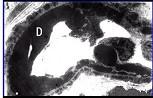

阅读下述三张狼疮性肾炎病理图片后,其病理诊断为 ( )A.Ⅲ型LNB.Ⅰ型LNC.Ⅳ型LND.Ⅴ型LNE.Ⅱ型LN

问题 阅读下述三张狼疮性肾炎病理图片后,其病理诊断为 ( )

选项 A.Ⅲ型LN B.Ⅰ型LN C.Ⅳ型LN D.Ⅴ型LN E.Ⅱ型LN

答案 C